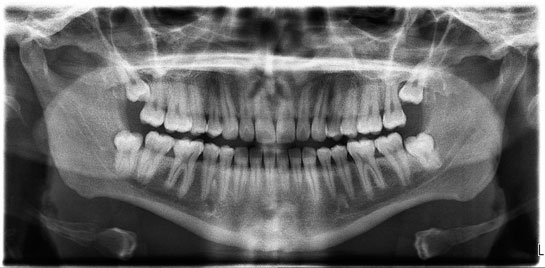

Diş Çekimi Sonrası Diş çekimi, diş hekimliği pratiğinde sıkça karşılaşılan bir prosedürdür. Dişin, çürük, enfeksiyon, aşırı aşınma veya ortodontik nedenlerle çekilmesi sonrası, hastalar bazı belirtiler ve durumlarla karşılaşabilir. Bu makalede, diş çekimi sonrası bakım, olası komplikasyonlar ve iyileşme süreci hakkında detaylı bilgi sunulacaktır. Diş Çekimi Sonrası Bakım Diş çekimi sonrasında hastaların dikkat etmesi gereken hususlar, iyileşme sürecini doğrudan etkilemektedir. Bu bakım süreçleri şunları içermektedir:

Olası Komplikasyonlar Diş çekimi sonrasında bazı komplikasyonlar gelişebilir. Bu komplikasyonlar arasında şunlar yer almaktadır:

İyileşme Süreci Diş çekimi sonrası iyileşme süreci, bireyden bireye değişiklik göstermekle birlikte genellikle aşağıdaki aşamalardan oluşur: